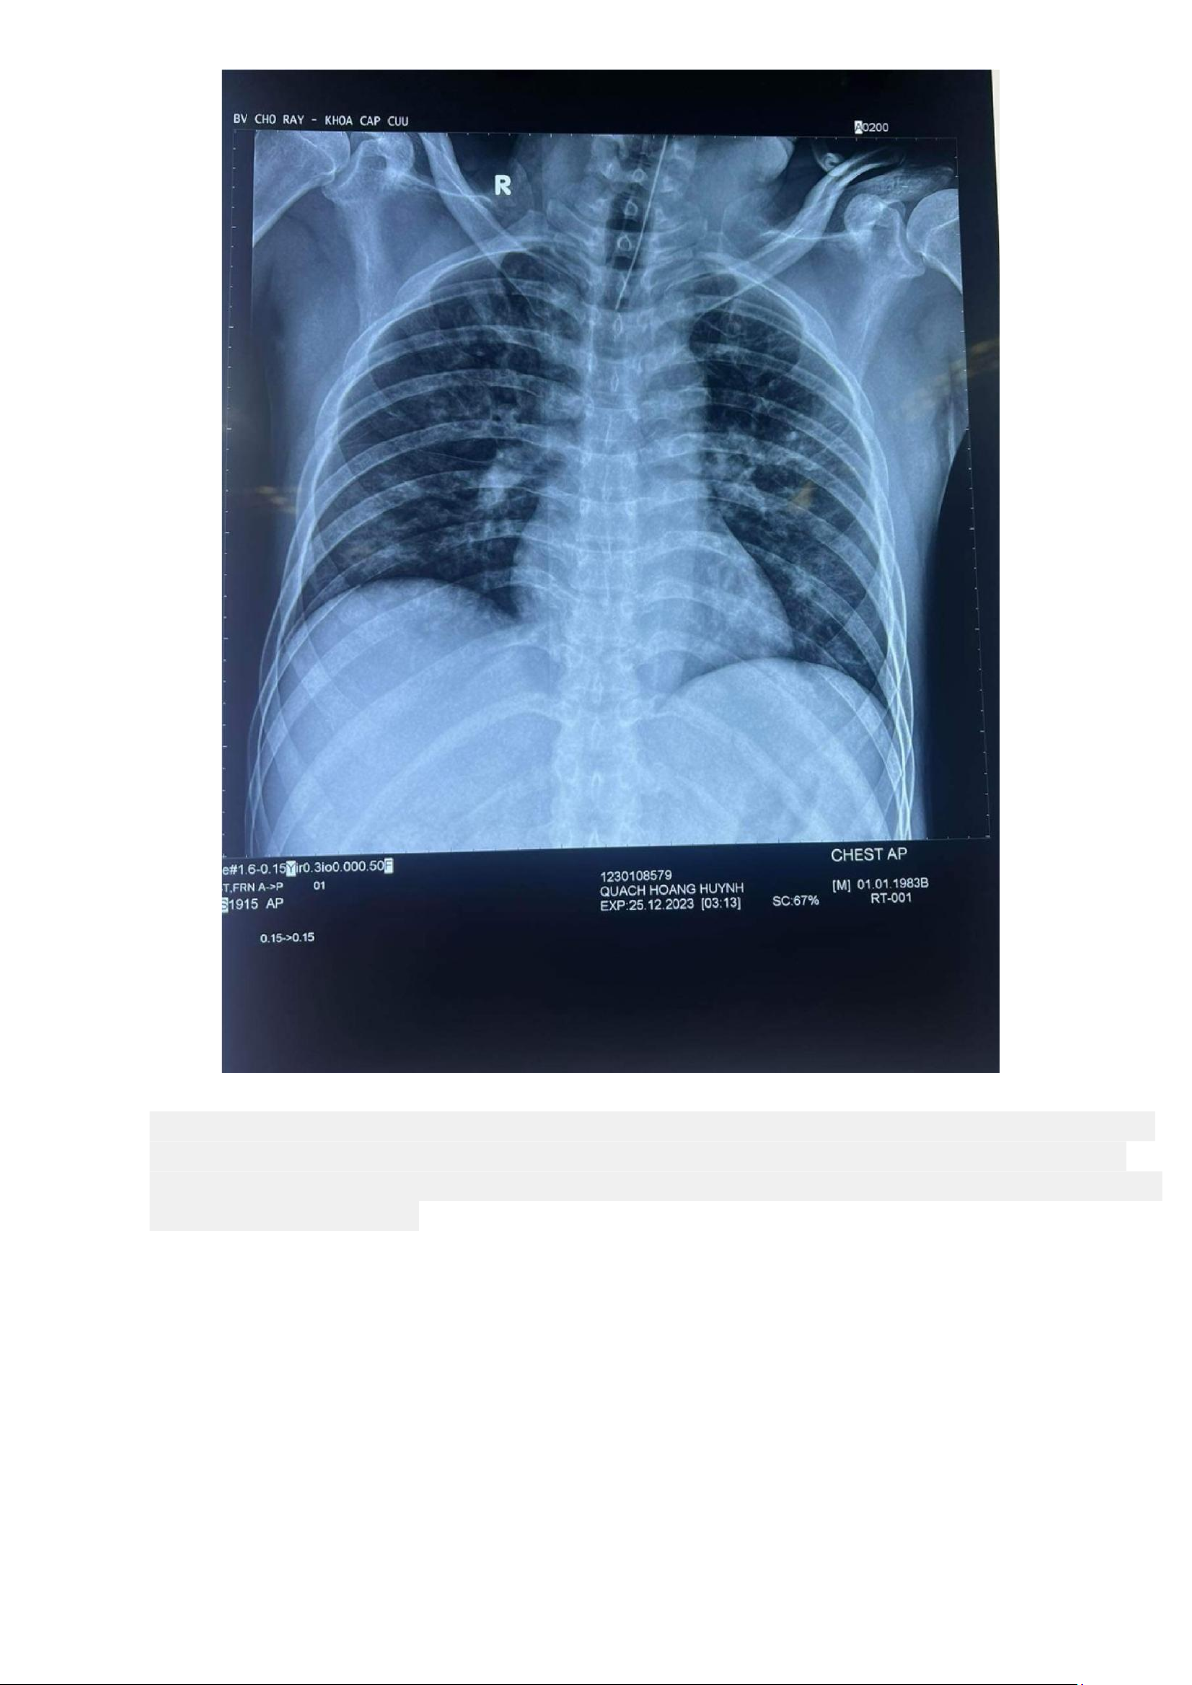

6. Xquang ngực thẳng 25.12.2023

Tổn thương phế nang dạng mô kẽ rải rác hai phổi, đặt NKQ đúng vị trí